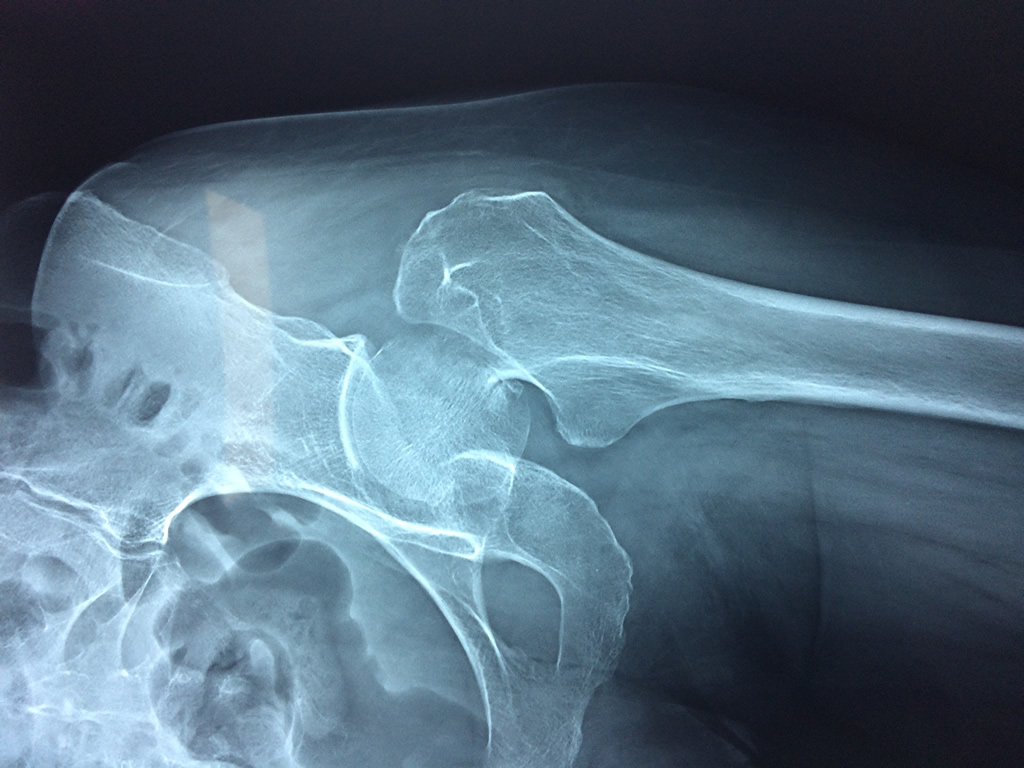

La cirugía de fractura de cadera se realiza para reparar una ruptura en la parte superior del hueso del muslo. Este hueso se denomina fémur.